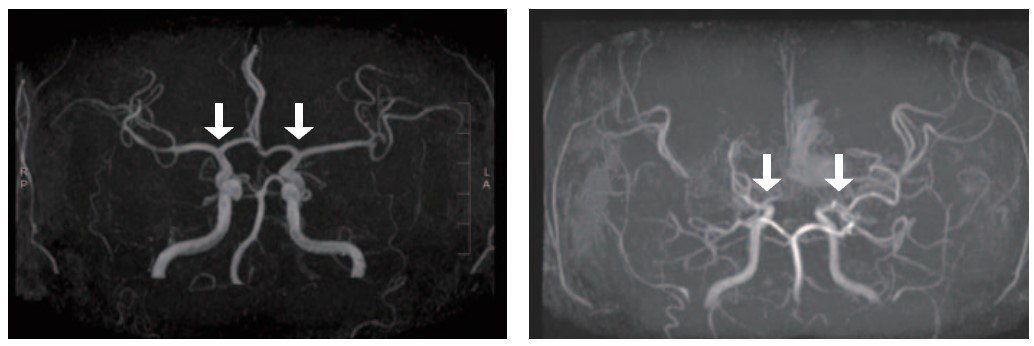

일반인의 뇌혈관(왼쪽)과 모야모야병 환자 뇌혈관(오른쪽). 자료 서울대병원